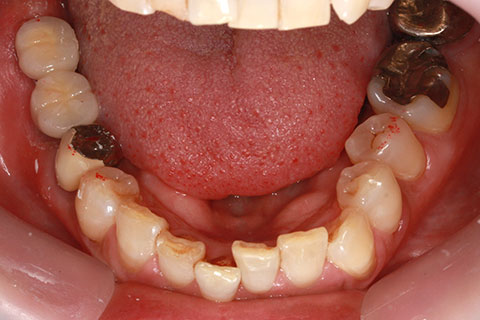

• 症例2

治療前

インプラント埋入時

治療後

年齢・性別

57歳男性

治療期間

3ヶ月

抜歯

なし

治療費

154万円

備考

左上5.6.7 及び左下6.7欠損

治療内容

左上5.6.7と左下6.7欠損部にインプラント埋入

施術の副作用(リスク)

オペによる知覚障害。インプラントによる歯肉炎。インプラント脱落。